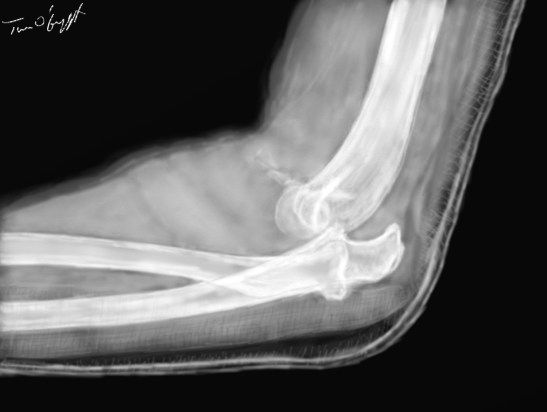

luxation postérieure du coude avec fracture du processus coronoïde du cubitus (radiographie de profil sous attelle plâtrée postérieure)